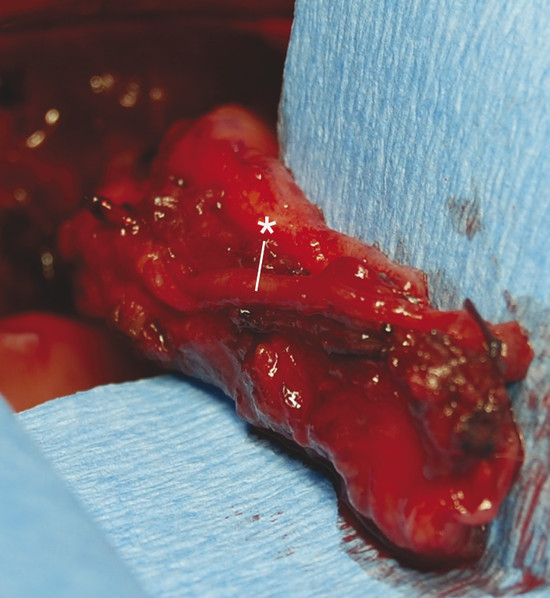

The FAMM flap is an intraoral cheek flap and includes the buccal mucosa, submucosa, buccinator muscle, and superficial layer of the orbicularis oris muscle (Fig. 18‑1). Superiorly based flaps are used for nasal septum perforations to maximize tissue length. Superiorly based FAMM flaps are pedicled on the angular artery and perfusion occurs through a retrograde flow. The facial artery is preserved on the entire length for the flap and kept attached to the buccinator muscle (Fig. 18‑2). The facial vein is usually not included in the flap as venous drainage is assured by a submucosal plexus. 24 The pivot point of flap is in the vicinity of the maxillary tuberosity or in the gingivolabial sulcus. The average width of the flap is 2.5 to 3 cm, and the pedicle base should be at least 1.5 cm to ensure adequate venous drainage. 17

The FAMM flap was first described by Pribaz et al in 1992 16 as a versatile musculomucosal flap harvested intraorally in the area of the jugal mucosa. It can be pedicled either inferiorly on the facial artery or superiorly on the angular artery. For the reconstruction of intranasal defects, a superiorly based pedicled FAMM flap will be harvested.